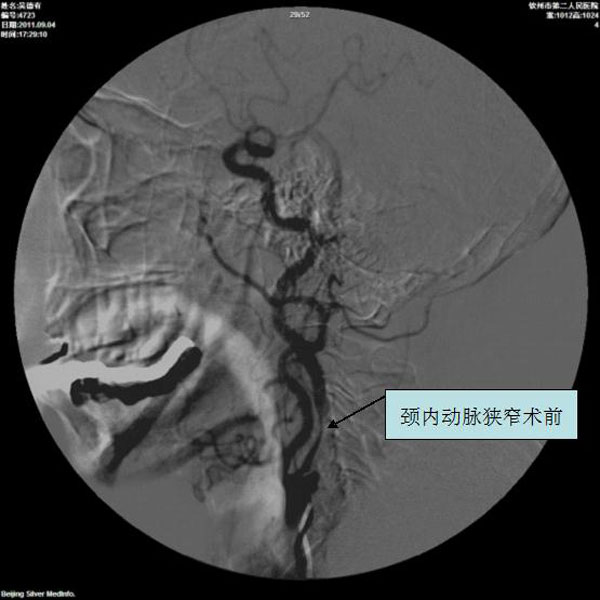

颈内动脉狭窄术前

颈动脉、椎动脉支架植入术

1.无症状动脉管径狭窄程度>70%。

2.有一过性缺血发作(TIA)或脑卒中发作症状,血管管径狭窄程度>50%。